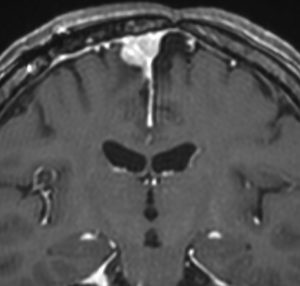

4歳の時に低線量頭蓋照射を受けていますが,医療関係の仕事について自立していた33歳の女性です。仕事中に記憶が飛ぶという症状がでて,周囲からおかしいと言われて受診しました。右の扁桃体のところ(左側のMRI)に海綿状血管腫ができていて,側頭葉てんかん(欠伸発作)を生じていました。バルプロ酸の投与で発作は止まって職場復帰しています。

放射線誘発髄膜腫

ジャーミノーマへ44グレイの全脳照射をしてジャーミノーマは治りました。でも,15年後に髄膜腫が発生しました。典型的な放射線誘発腫瘍です。これは取れるので大丈夫!